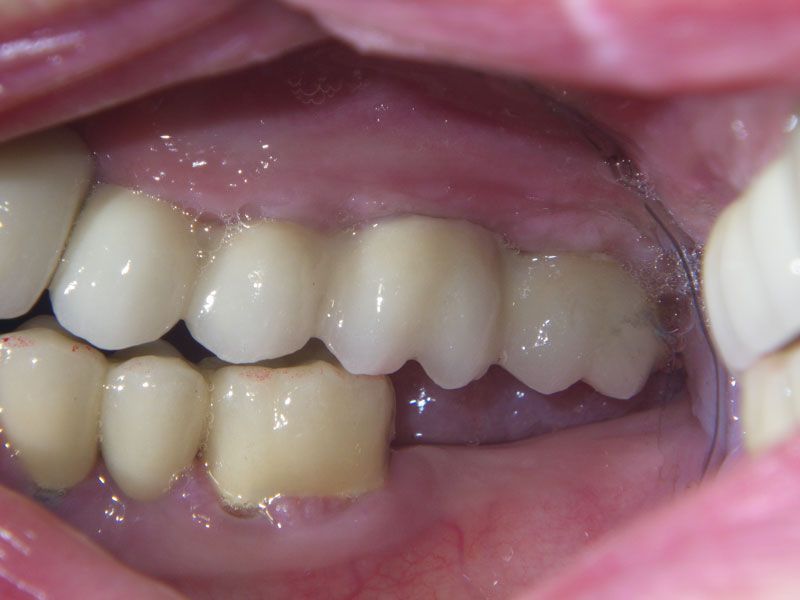

Протезирование было проведено с помощью трех мостовидных протезов, причем выбор цвета и формы зубов был предоставлен пациенту. Оказалось, что высоко-эстетичнын зубы, были мечтой пациентки всю жизнь. Они и были выбраны. Диссонанс с собственными зубами, которыми так дорожила наша пациентка до операции, оказался столь сильным, что теперь в планах пациентки заняться нижней челюстью в плане функционально-эстетическойй реабилитации фронтального участка несъемным протезированием на имплантах.